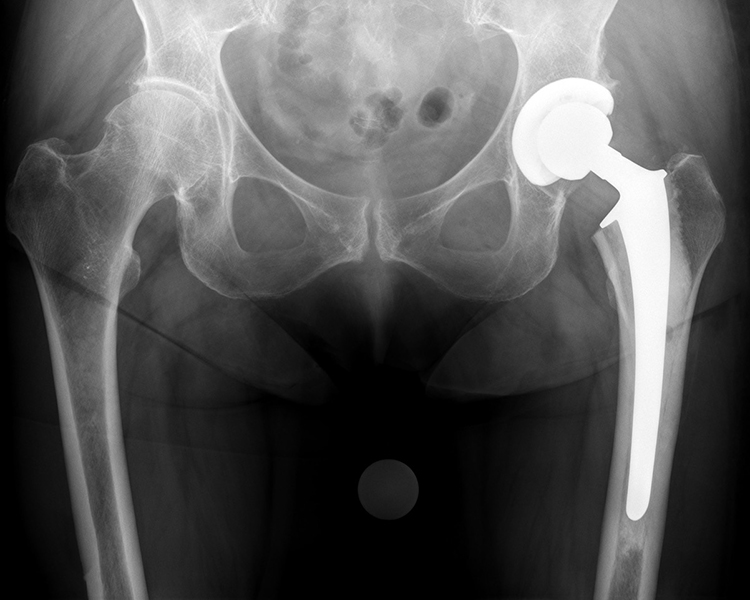

zementfreie Hüftendoprothesen

zementfreie SPCL Schaftprothese mit zementfreier Pfanne (Firma Link)

Hybrid-Hüftendoprothese (zementierter SP II-Schaft mit zementfreier Pfanne, Fa. Link)